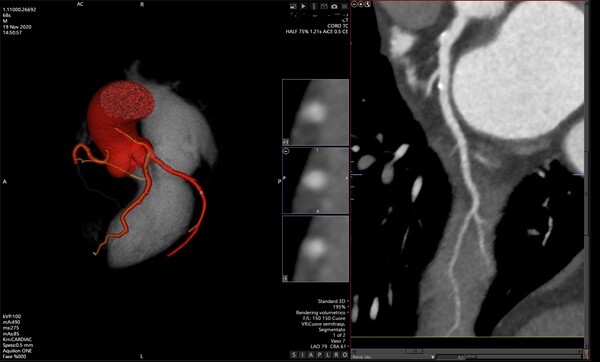

Entrando più nello specifico la Tac cardiaca produce immagini dettagliate a “strati” del cuore, consentendo ai medici di valutare la presenza di eventuali anomalie, restringimenti o calcificazioni nelle arterie. Come il suo nome indica questo esame si basa sul principio della tomografia computerizzata, una tecnologia che acquisisce numerose immagini radiografiche da diverse angolazioni.

Tutto mentre il paziente si trova sdraiato su un lettino. Il lettino scorre lentamente all’interno di un apparecchio a forma di anello, chiamato scanner, che ruota attorno al torace. Durante la scansione, un computer elabora tutte le immagini raccolte e le ricostruisce in modelli tridimensionali estremamente dettagliati del cuore e dei vasi sanguigni.

Per rendere le immagini ancora più chiare, nella maggior parte dei casi viene utilizzato un mezzo di contrasto a base di iodio. Questa sostanza viene iniettata in una vena del braccio e permette di evidenziare meglio il flusso del sangue all’interno delle arterie coronarie. Dobbiamo ricordare che il mezzo di contrasto rende più visibili eventuali restringimenti o ostruzioni, che possono essere causati da aterosclerosi. Ovvero da depositi di grasso e calcio nelle pareti dei vasi sanguigni.